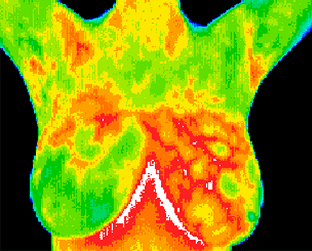

Just like a fingerprint is unique to each person, each one of us has a particular infrared heat map of our body. By using this